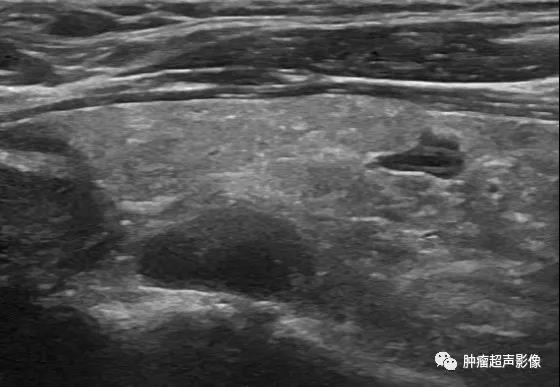

慢性肾脏疾病,血PTH升高,左侧2个(上图)、右侧1个(下图)增大的甲状旁腺腺体,呈边界清的低回声,与甲状腺分界清晰,其中两个内见钙化。